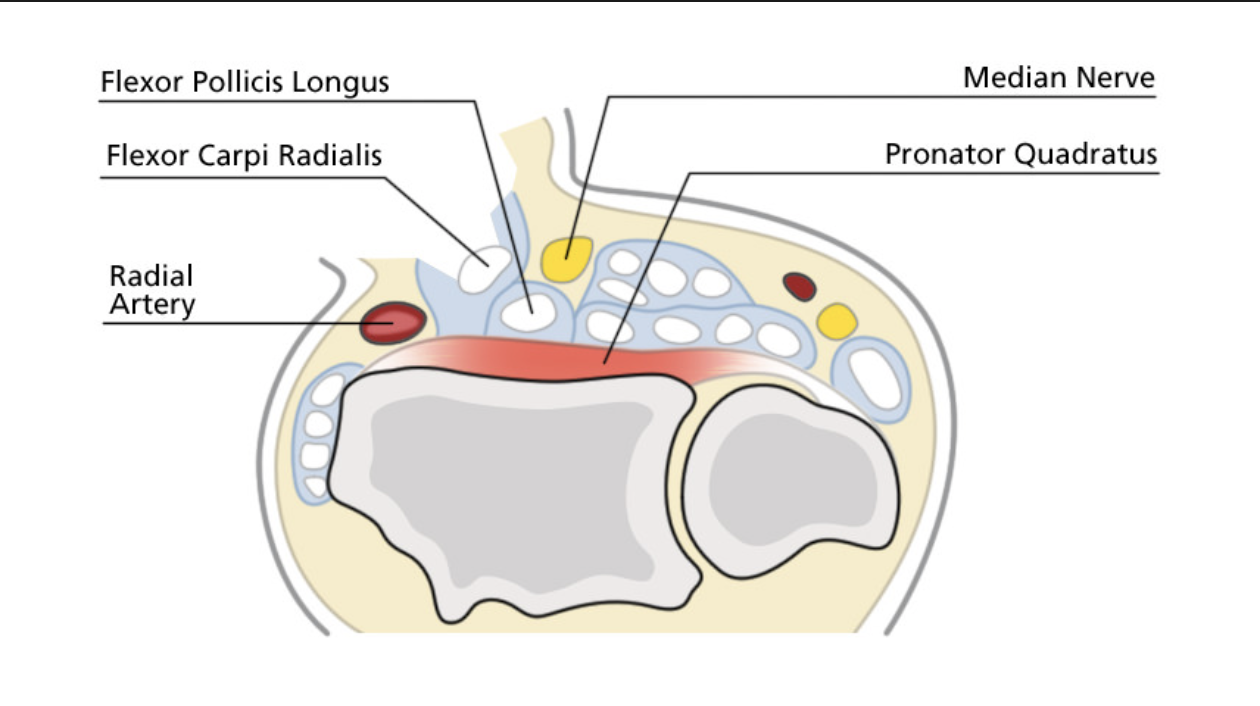

FCR Approach to the Distal Radius

Interval: FCR (Median N.) and Radial a. (brachioradialis- radial n.)

Approach:

- Sharp incision over FCR tendon, sharply through skin, subcutaenous tissue and FCR sheath. Retract FCR tendon radially and incise through FCR subsheath.

- Retract FPL tendon ulnarly

- Incise PQ along distal and radial boarder and peel off subperiosteally to reveal distal radius

Dangers: Radial A., Median N.